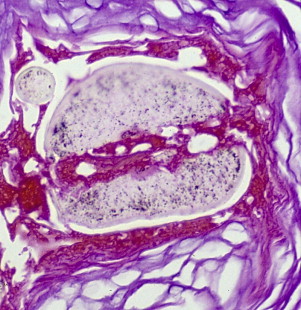

Subtle Clues to the Diagnosis of Trichotillomania

Histologic features of trichotillomania (trichotillosis) include empty anagen follicles, multiple catagen hairs, pigment casts in the follicular channel, and trichomalacia. Of these, the most specific finding is trichomalacia, which can produce striking findings, such as the “hamburger bun sign.” This involves a vertically oriented split in the hair shaft, containing proteinaceous material and erythrocytes, morphologically reminiscent of a hamburger in a bun ( Fig. 4 ). Degeneration of the hair fiber can take other forms, such as the “hot dog” sign ( Fig. 5 ).